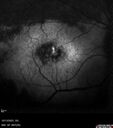

Central Retinal Vein Occlusion - Non-Ischemic - Excellent Outcome17 views57 year old man The right eye has had vision loss for about 3 weeks. He woke up with vision loss.

Medical Hx: HIV . Diabetes Mellitus (since 2014). Thyroid Disease.

Systemic Meds: gemboya. Metformin Hydrochloride. trulicity. losartan. vesepa. Synthroid .

VA OD: sc20/160 OS: sc20/20

TP: OD:14 OS:14

Treated with Avastin

VA 6 weeks later 20/32 – dry one shot.

Missed follow-up after second treatment and came 5 months later with good vision and no macular edemaAug 17, 2025